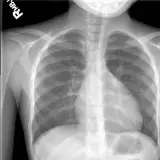

Des cas entièrement interactifs avec les outils attendus d'un PACS — défilement, fenêtrage, zoom, déplacement, mesures, ROI et mode plein écran.

Des annotations détaillées mettent en évidence les résultats clés directement sur les cas. Cliquez sur les résultats liés dans les descriptions de cas pour accéder à leur emplacement exact sur l'examen.

Défilez, déplacez, fenêtrez et zoomez comme sur une station PACS de travail